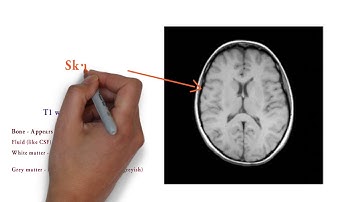

What’s the Difference Between an MRI and a CT?